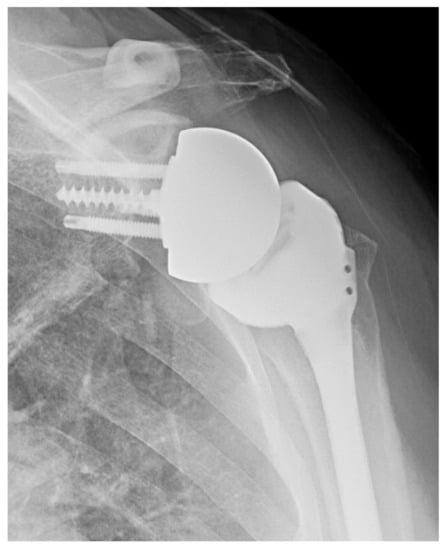

2.1.1. Stemless Implants

2.1.3. Convertible Platforms

3.1. Combined Humeral and Glenoid Component Innovations

Lateralization

3.2. Humeral Component Innovations

3.2.1. Stemless Implants